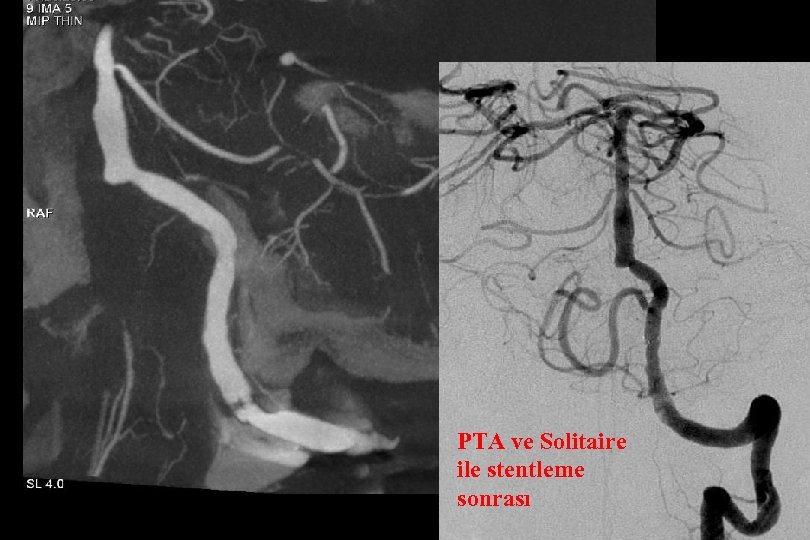

PTA ve Solitaire ile stentleme sonrası